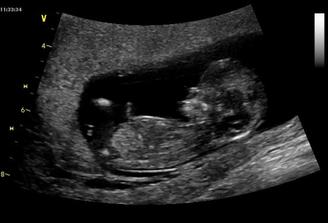

06/10/ bije srdííčko !!!!

16+1 geneticka konzultace OK,nemusíme na AMC

Zaplatila jsem si ale přesto UTZ a vypada to,že budeme mit chlapečka 🙂) pry tak na 80% jistota je vždy až po porodu 🙂)

CHLAPEČEK POTVRZENY Dr Břeštákem ))